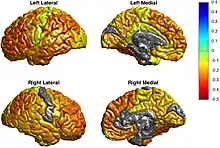

A 2016 meta analysis reported that bipolar disorder was associated with grey matter reductions bilaterally in the ACC, vmPFC, and insula extending to the temporal lobe. When compared with grey matter reductions in unipolar depression, significant overlap occurred in the insular and medial prefrontal regions. Although unipolar depression was associated with reductions in the ventral most and dorsal most regions of the mPFC and bipolar with a region near the genu of the corpus callosum, the overlap was still statistically significant.[59] Similar to the overlap with major depression, a significant overlap of bipolar disorder with schizophrenia in grey matter volume reduction occurs in the anterior cingulate cortex, medial prefrontal cortex, lateral prefrontal cortex and bilateral insula.[60]

A 2010 meta analysis of differences in regional grey matter volume between controls and bipolar disorder reported reductions bilaterally in the inferior frontal cortex and insula, which extended more prominently in the right side to include the precentral gyrus, as well as grey matter reductions in the pregenual anterior cingulate cortex (BA24) and anterior cingulate cortex (BA32).[61] One meta analysis reported enlargement of the lateral ventricles and globus pallidus, as well as reductions in hippocampus volume and cross sectional area of the corpus callosum.[62] Another meta analysis reported a similar increase volumes of the globus pallidus and lateral ventricles, as well as increased amygdala volume relative to people with schizophrenia.[63] Reductions have also been reported in the right inferior frontal gyrus, insula, pars triangularis, pars opercularis, and middle and superior temporal gyrus.[64] Structural neuroimaging in people who are susceptible to bipolar disorder (i.e., have a number of relatives with bipolar disorder) have produced few consistent results. Consistent abnormalities in adult first degree relatives include larger insular cortex volumes, while offspring demonstrate increased right inferior frontal gyrus volumes.[65]

The ENIGMA bipolar disorder working group reported cortical thinning in the left Pars opercularis (BA44-inferior frontal gyrus), left fusiform gyrus, left rostral middle frontal cortex, right inferior parietal cortex, along with an increase in the right entorhinal cortex. Duration of illness was associated with reductions bilaterally in the pericalcarine gyrus, left rostral anterior cingulate and right cuneus, along with increases in the right entorhinal cortex. Treatment with lithium was associated with increased cortical thickness bilaterally in the superior parietal gyrus, left paracentral gyrus, and left paracentral lobule. A history of psychosis was associated with reduced surface area in the right frontal pole.[54] Another study on subcortical abnormalities by the same research group reported reductions in the hippocampus, amygdala, and thalamus, along with ventricular enlargement.[66]

Frontal cortex

Different regions of the ACC have been studied in the literature, with the subgenual (sgACC) and rostral (rACC) parts being largely separated. Grey matter volume in the sgACC has been, albeit with some exceptions, found to be reduced in bipolar. Along with this, bipolar is associated with increased blood flow in the sgACC that normalizes with treatment. Congruent with these abnormalities is a reduction in glial cells observed in post mortem studies, and reduced integrity of white matter possibly involving a hemispheric imbalance. Findings in the rACC are largely the same as the sgACC (reduced GM, increased metabolism), although more studies have been carried out on protein expression and neuronal morphology. The rACC demonstrates reduced expression NMDA, kainate and GABA related proteins. These findings may be compensating for increased glutaminergic afferents, evidenced by increased Glx in MRS studies. One VBM study reported reduced grey matter in the dACC. Inconsistent results have been found during functional neuroimaging of cognitive tasks, with both decreased and increased activation being observed. Decreased neuron volume and a congruent increase in neural density have been found in the dACC. Reduced expression of markers of neural connectivity have been reported (e.g. synaptophysin, GAP-43), which is congruent with the abnormal structural connectivity observed in the region. [80]

The orbitofrontal cortex demonstrates reduced grey matter, functional activity, GAD67 mRNA, neuronal volume in layer I, and microstructural integrity in people with bipolar.

Although the role of acute mood states is unknown, grey matter volume is generally reported as reduced in the dlPFC, along with resting and task evoked functional signals. Signals of myelination and density of GABAegic neurons is also reduced in the dlPFC, particularly in layers II-V.[81]